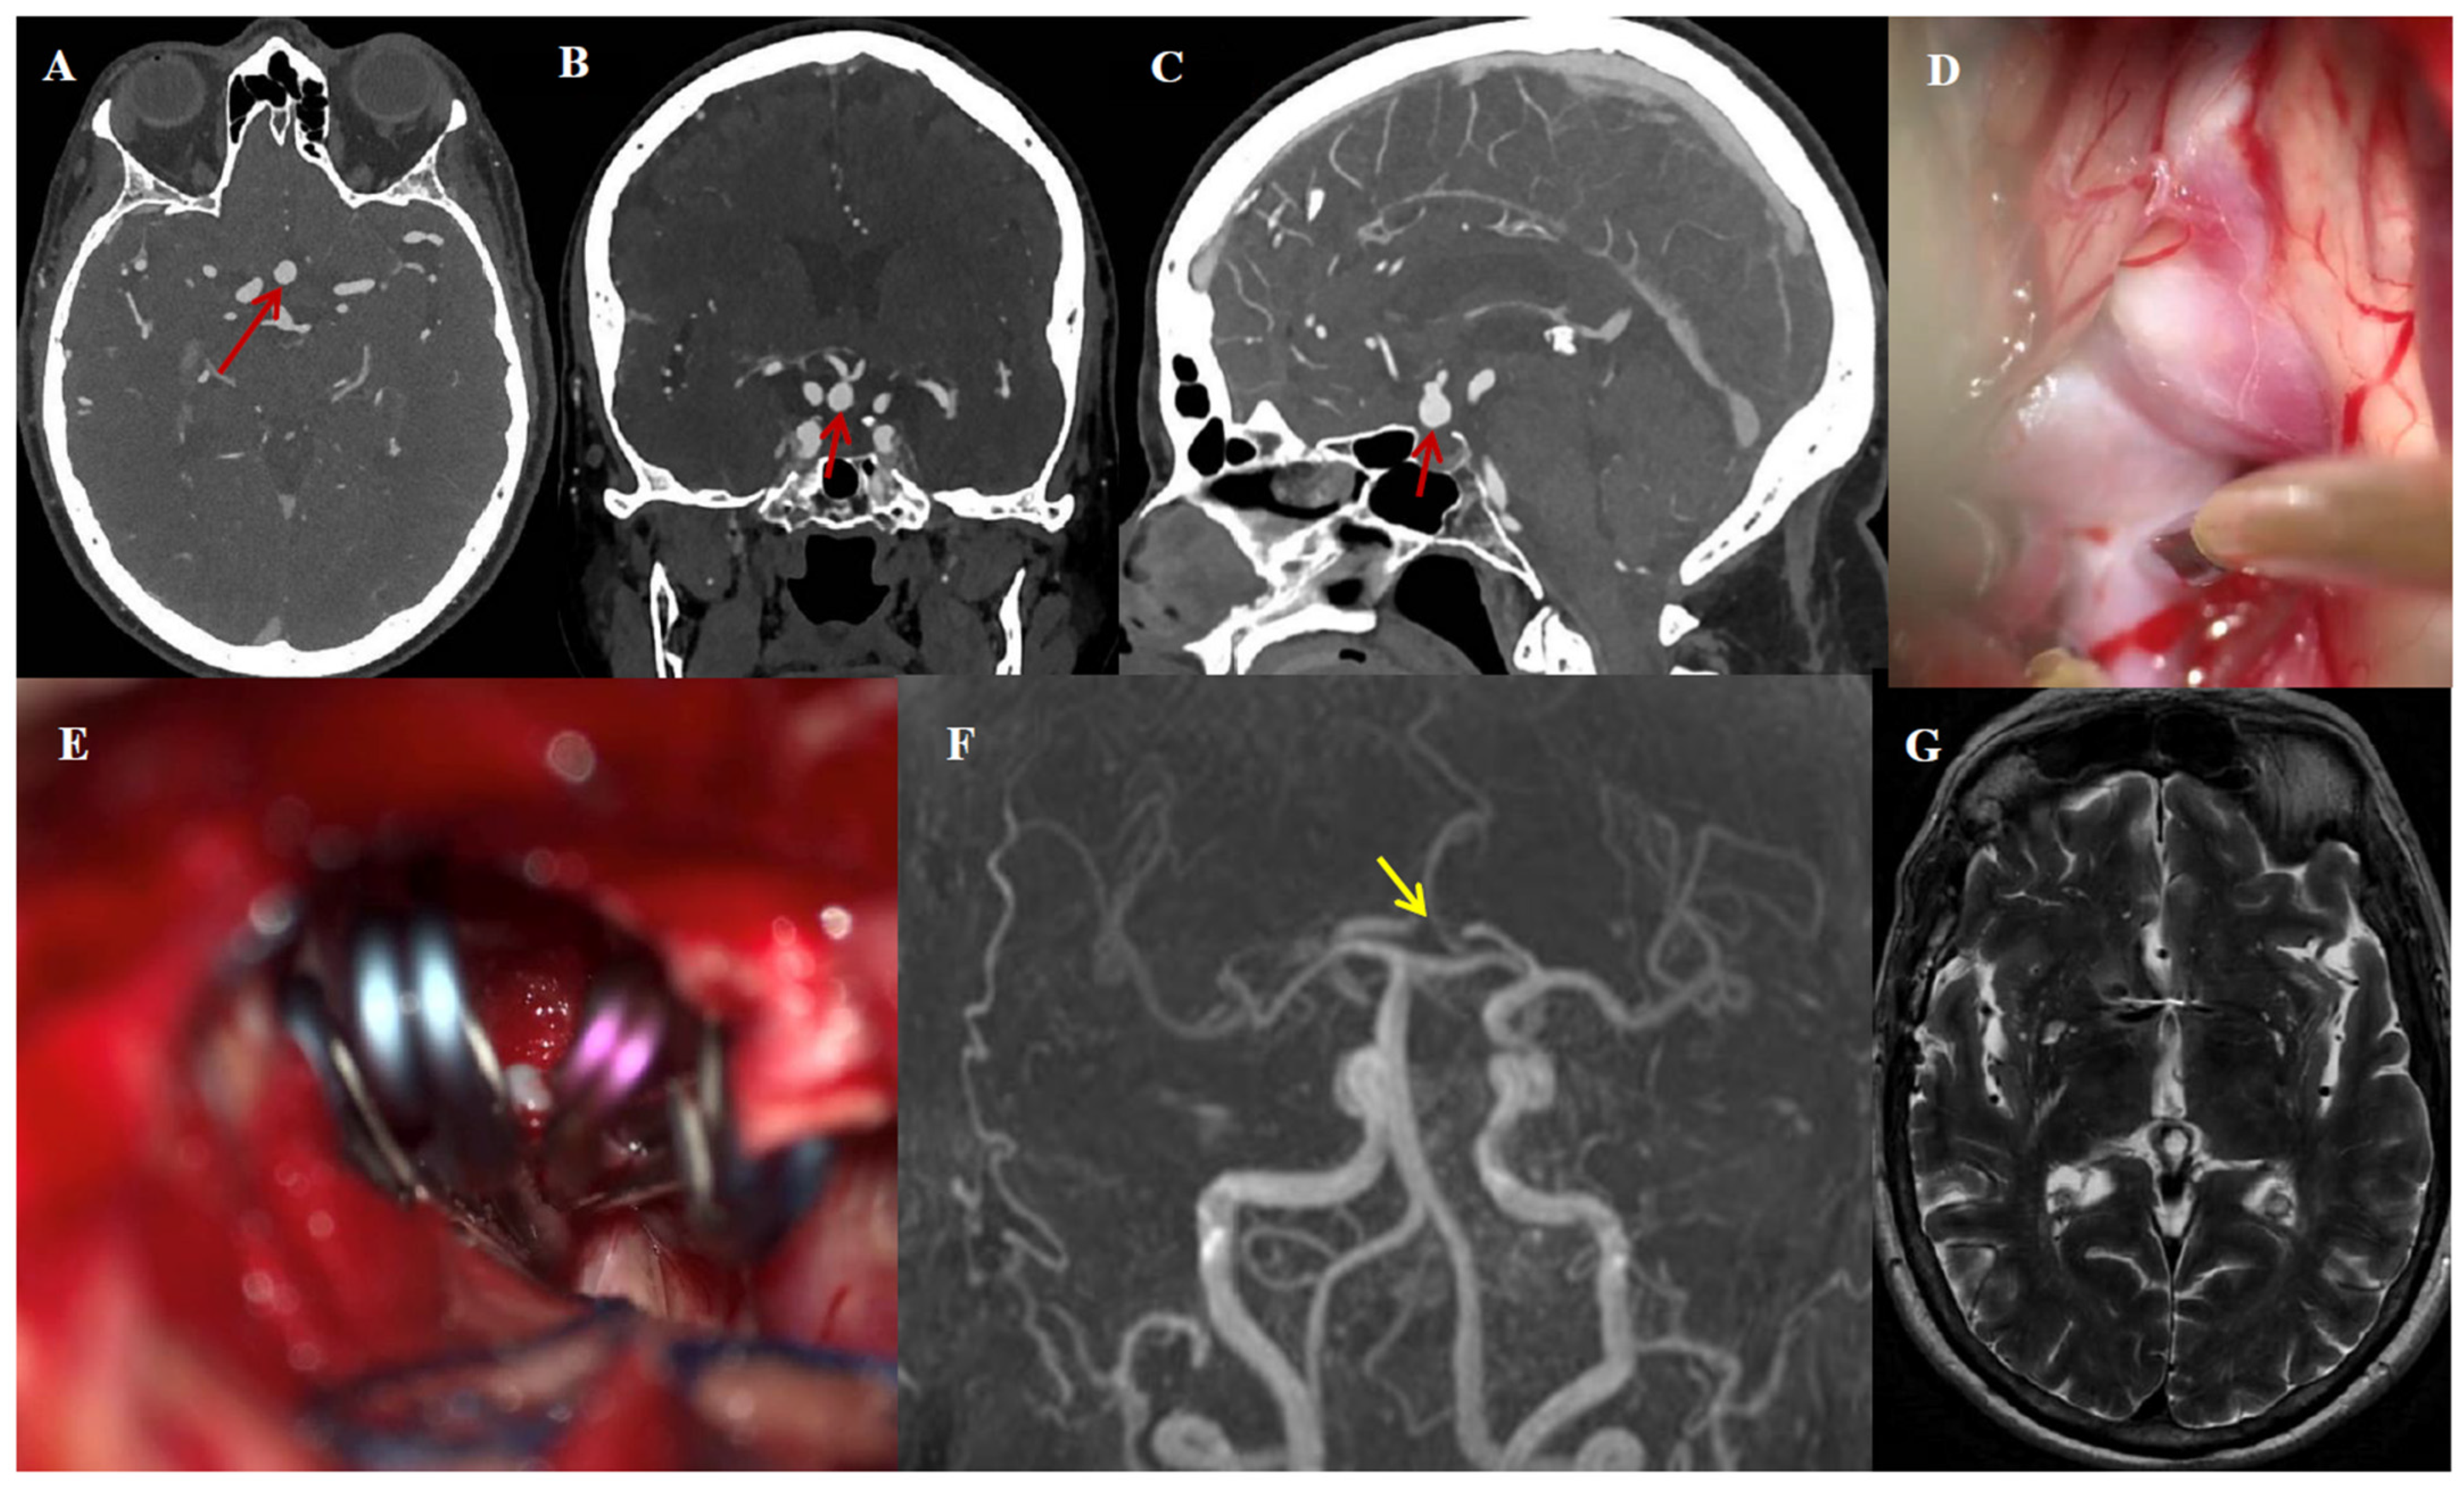

3.5. Illustrative Case #1